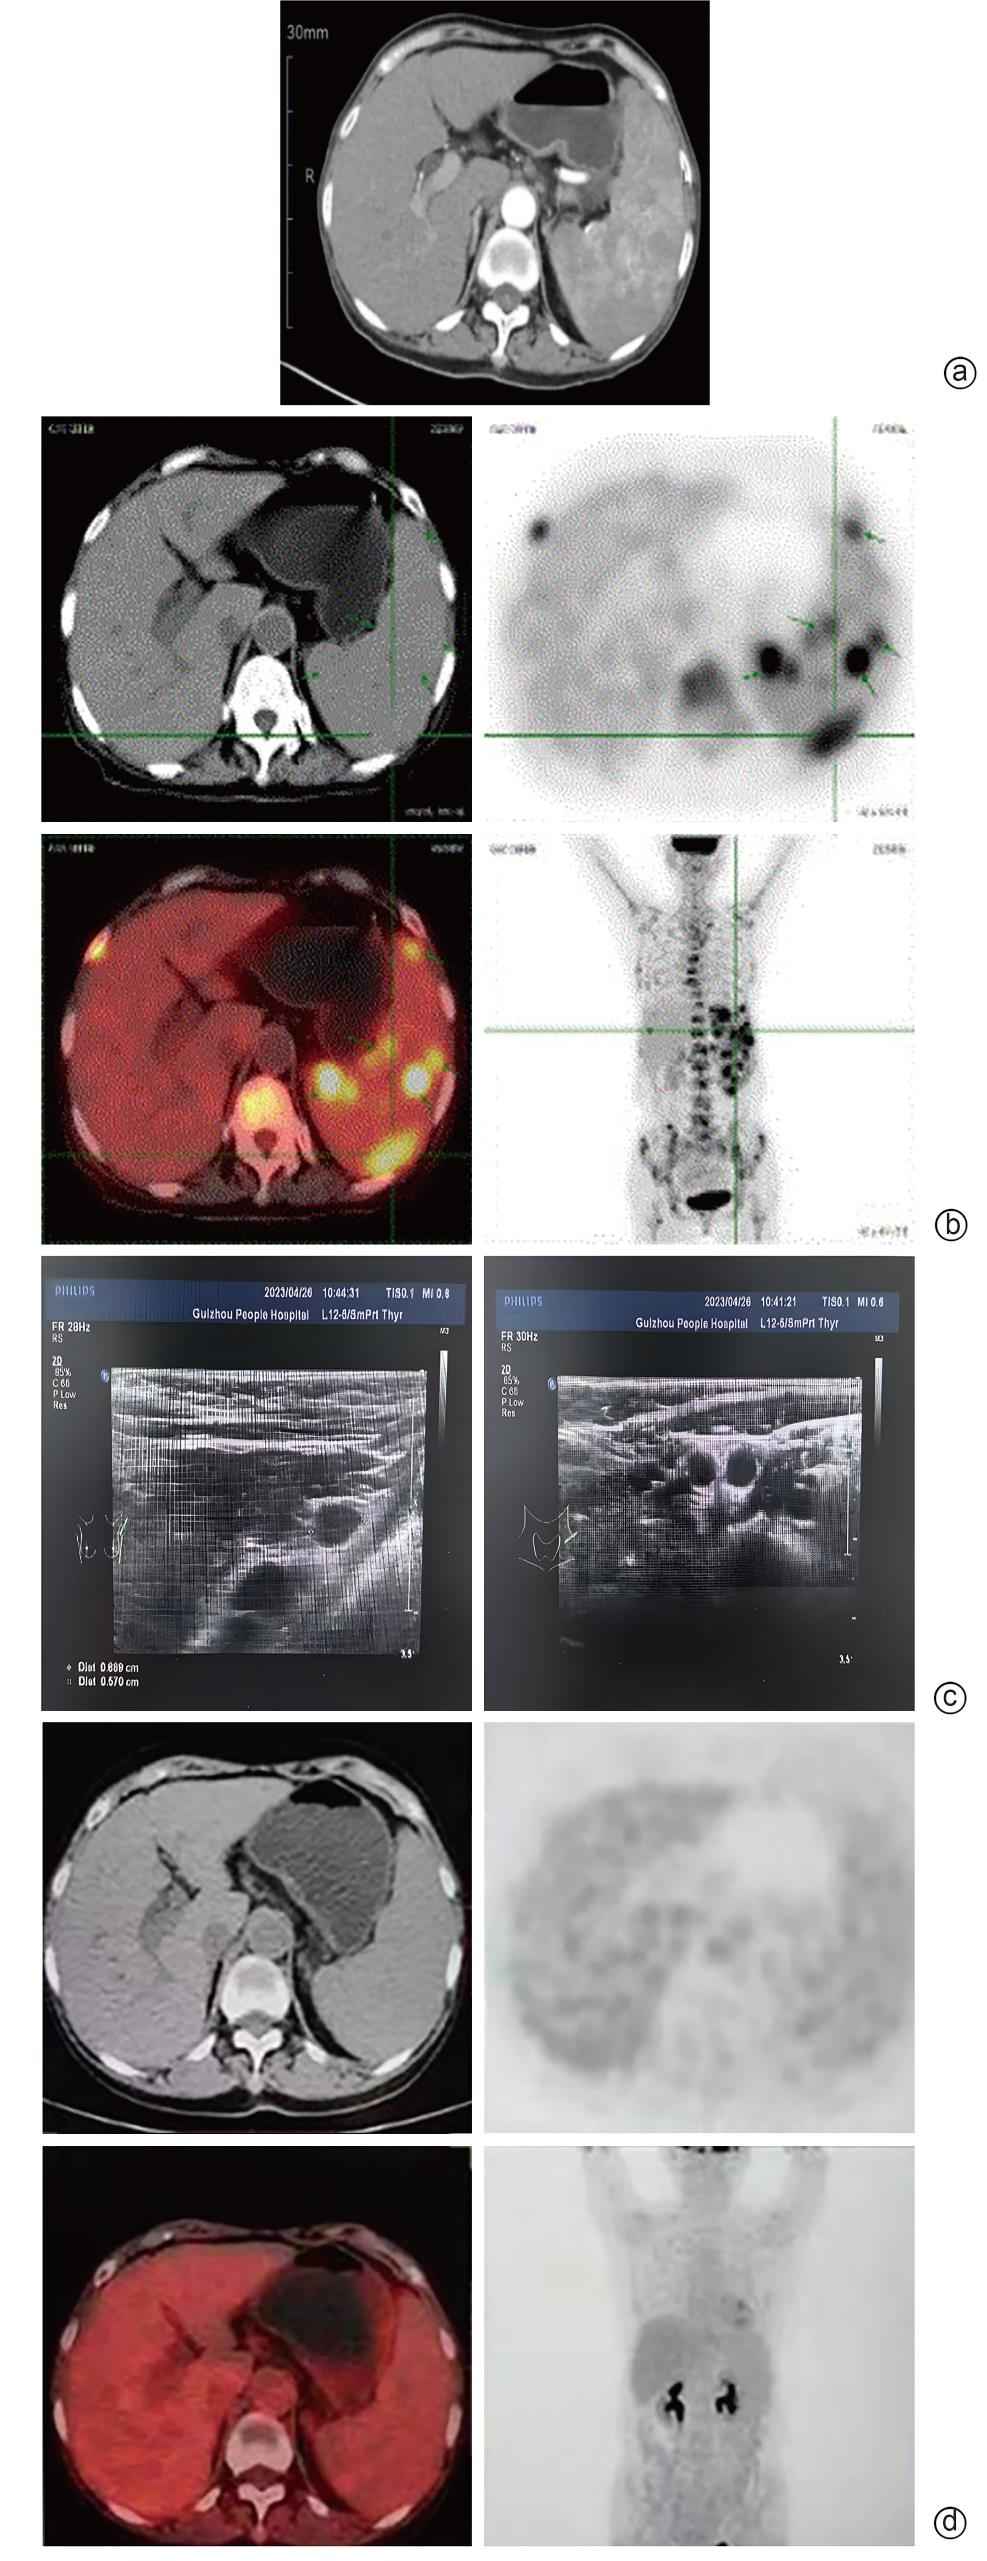

原发性脾淋巴瘤误诊为干燥综合征合并肝硬化1例报告

李成成, 刘渝洪, 王路, 彭虹, 罗新华, 李宏

2025, 41(9): 1883-1887. DOI: 10.12449/JCH250925

摘要:

原发性脾淋巴瘤是一类罕见的恶性肿瘤,临床表现与干燥综合征、肝硬化存在一定的相似性,易导致误诊。本个案报道1例被误诊为干燥综合征合并肝硬化的原发性脾淋巴瘤患者,以加深对原发性脾淋巴瘤、干燥综合征及肝硬化的认识,以免误诊及延误治疗。